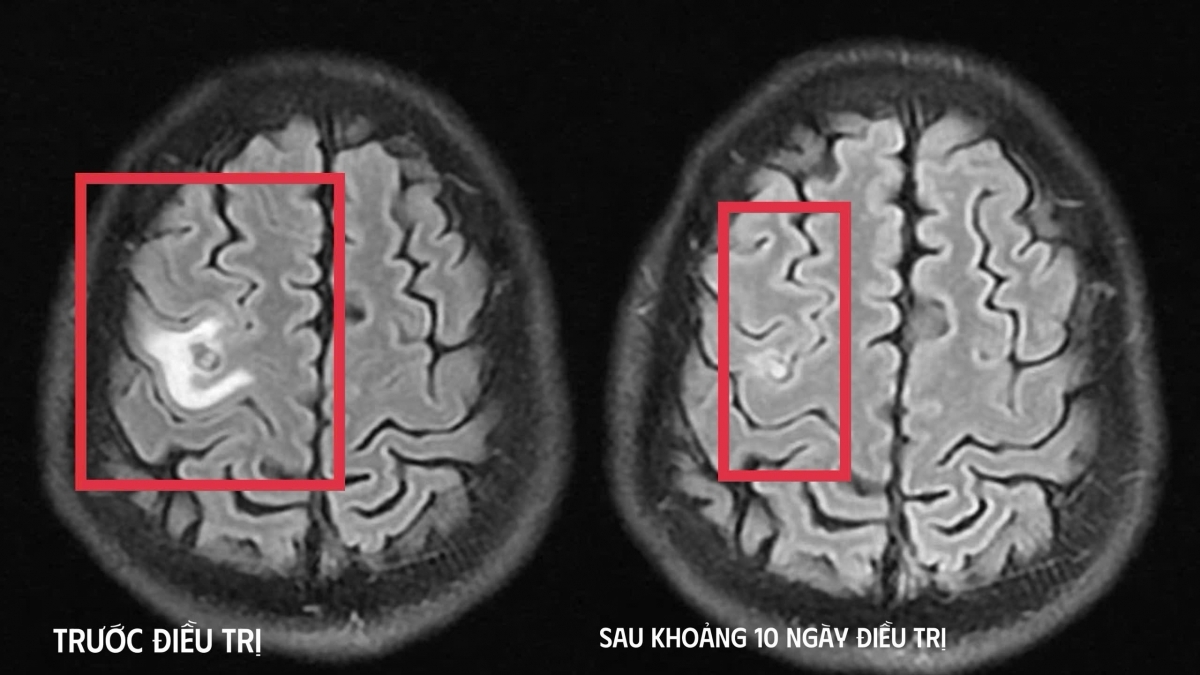

Sau khi chụp cộng hưởng từ sọ não, phát hiện có tổn thương dạng nang nhỏ tại thùy trán trái, kích thước khoảng 11 x 7mm, xung quanh có phù não nhẹ. Hình ảnh này hướng nhiều đến tổn thương do ký sinh trùng hơn là u não nguyên phát. Xét nghiệm huyết thanh học sau đó phát hiện bệnh nhân bị nhiễm sán gây tổn thương não.

Sau khoảng 10 ngày điều trị tình trạng bệnh nhân cải thiện rõ rệt, hết tê tay, không còn xuất hiện cơn co giật, không đau đầu hay chóng mặt, toàn trạng ổn định. Anh T. được cho ra viện tiếp tục điều trị ngoại trú đủ liệu trình kéo dài 4 tuần.